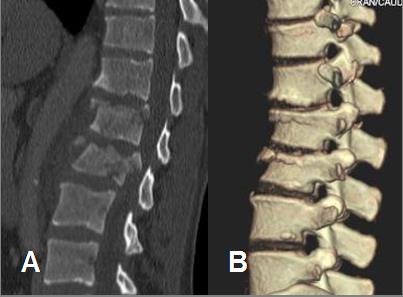

La prueba inicial es la radiología simple, nos dirá si hay fractura y el tipo. Según esta tendremos que hacer algún tipo de prueba complementaria más.

El TAC nos ayuda también sobre todo en las características óseas de la fractura.